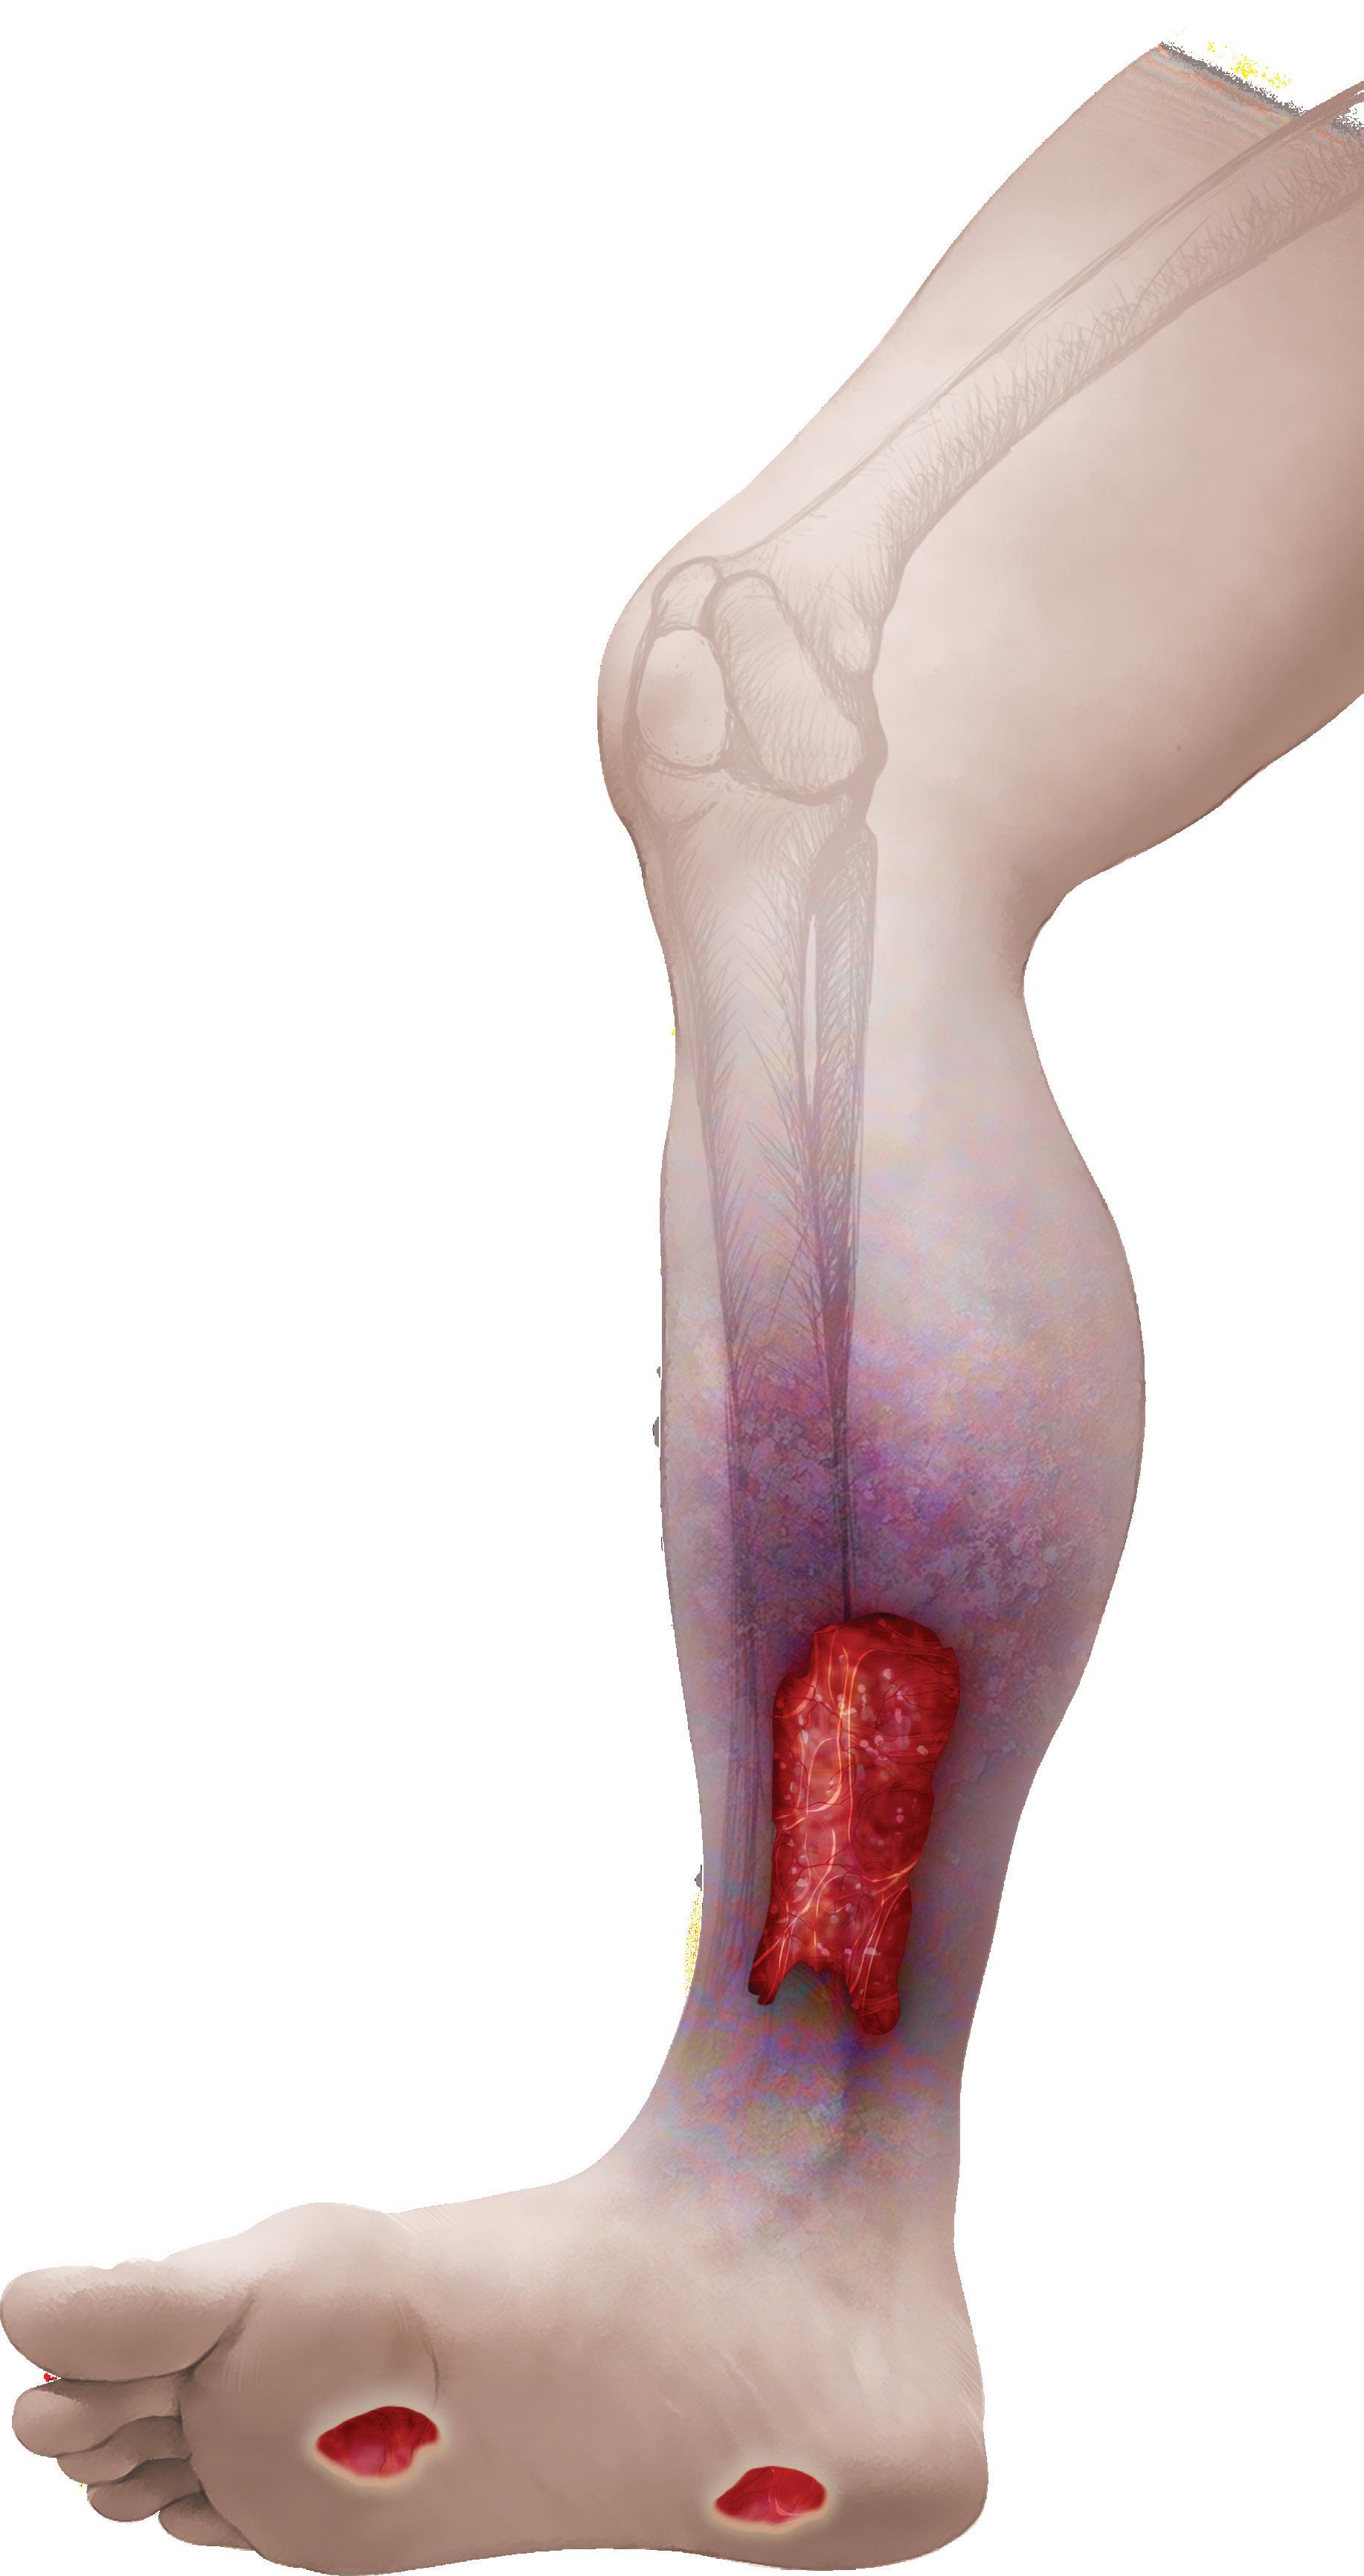

Removing in-stent thrombosis with the RevCore Thrombectomy

Catheter

For patients with in-stent thrombosis (IST), one of the most critical unmet needs has been an effective method to remove acute-to-chronic material. Here, Rishi Roy, MD, a vascular surgeon at Advanced Vascular & Vein Associates in Flowood, Mississippi, discusses his experience with the first mechanical thrombectomy device to be able to do so—the RevCore thrombectomy system. RevCore is a minimally invasive, over-the-wire device indicated to treat thromboemboli in the peripheral vasculature, including venous stents. It includes a catheter with an expandable element for venous stent treatment. It also has a reinforced catheter shaft for precise movements and a diameter-control knob for adjusting the element to treat vessels 6mmplus and venous stents from 10–20mm.

Prior to RevCore, how did you treat in-stent thrombosis?

Previously I would take a multimodal approach using suction thrombectomy, along with balloon venoplasty, or even a non-compliant balloon. The goal was to get some lumen gain, to restore some outflow to decompress the limb.

How does this new device work?

RevCore makes it possible to extract thrombotic material from an occluded stent. The diameter of the coring element can be increased or decreased manually to accommodate the size of the vessel . You engage or disengage with the stent, as needed, and you can be more aggressive as you work through the material that caused the occlusion.

How do you size the catheter and capture liberated clot?

nal stent diameter, that patient will require close follow-up every six months or so, but they may be able to go for a couple of years between interventions. Fewer interventions also means decreased anesthesia time, operative time, chance of adverse events and morbidity. If we can decrease the number of cases because we’re able to remove IST in a single procedure, that’s a game changer.

Initial IVUS confirmed the IST (A). Preprocedure venogram demonstrated instent thrombosis and impaired flow (B). Extracted thrombotic material (C). Postprocedure IVUS confirms stent patency (D). Postprocedural venogram confirms patency (E). RevCore Thrombectomy Catheter with expandable coring element (F)

is new, I have an intensive follow-up protocol and, working with a wound care group, even closer follow-up is possible. I generally see the patient back in four weeks. After that, we see them at three and six months, and then every six months. If over a twoyear period we don’t see recurrent stenosis, and the patient is comfortable, we could get it down to once a year.

What anticoagulation regimen do you give these patients?

Case report: Complete thrombus extraction after severe right EIV stent stenosis

Patient history

When sizing the element in the stent, low and slow is key. There is a tactile feel to the device when “revving,” and it’s important to note resistance level. Some resistance is good—too much means the element is likely oversized and should be decreased by turning the external diameter-control knob to the minus sign on the handle. An important consideration for these cases is to have another device placed in the inferior vena cava (IVC) to capture the cleared material.

When do you know that RevCore worked?

Immediately postprocedure, I can gauge whether the device worked when I visualize blood flow on imaging. Because the device

I send them out on either a novel oral anticoagulant (NOAC) or Coumadin. You know, people often ask me, “Which do you prefer?” My honest answer is I prefer whatever the patient can afford. Because if they can’t afford a NOAC, then they’re not going to take it, and we’re back at square one.

How do you think RevCore will change the treatment pathway?

RevCore allows us to consider intervention sooner for patients who are suffering from symptoms related to IST. Some had stents placed when they were in their 20s or 30s, and when these stents are put in, they’re in forever. Now it’s decades later, and they have recurrent IST with chronic material that requires reintervention every threesix-eight months for symptom relief. Now, if we can debulk and get back to the origi-

A FlowTriever catheter (Inari Medical) was advanced over a stiff wire to the infrarenal segment of the IVC, and two of the catheter’s XL disks were deployed. From the right side, a stiff wire was advanced to the IVC via a Bern catheter (Boston Scientific), followed by an Amplatz wire. The catheter was removed, and then a 16F sheath was placed.

IVUS was performed in the IVC, revealing that the stent extended into the very distal IVC; no stenosis was seen. IVUS of the right common iliac vein (CIV) showed overlapping stents but no stenosis. A venous ultrasound probe inserted to the level of the right EIV showed 50–60% stenosis. IV heparin was administered.

The RevCore catheter was advanced over the Amplatz wire to the right EIV, and the coring element was deployed within the stent in an unexpanded state. The coring element was then slowly enlarged and rotated, loosening the material within the stent. RevCore was then withdrawn and cleaned. A Triever16 Curve catheter (Inari Medical) was advanced and suction thrombectomy performed, removing a combination of subacute and chronic thrombotic material (C). Balloon venoplasty of the stented portion of the right CFV, EIV and CIV was performed with an 18mm noncompliant balloon.

Additional passes with the Triever16 Curve catheter were conducted along the right iliac segments and within the IVC, removing thrombotic material that had been captured by the FlowTriever XL disks. Thrombus capture with either FlowTriever XL disks or the Protrieve sheath is critical to the RevCore procedure. Blood was returned to the patient using FlowSaver.

A man in his mid-50s presented with ulceration and swelling in his right foot with the intention to transfer care. Several months prior, a right external iliac vein (EIV) to right common femoral vein (CFV) stent had been placed. A venous duplex ultrasound study showed proximal stent occlusion and non-occlusive venous thrombosis in the left proximal femoral, popliteal, posterior tibial, and gastrocnemius vessels, as well as thrombosed varicosities. Right lower extremity venography and intravascular ultrasound (IVUS) performed two-and-a-half weeks later confirmed 65% stenosis of the left EIV stent (image A). An in-hospital mechanical thrombectomy and balloon angioplasty procedure was planned.

Procedural overview

The patient was positioned supine and ultrasound guidance was used to access the right CFV. A J-wire was advanced into the IVC. An 8F sheath was placed and a venogram showed stenosis within the right EIV stent (B). Similarly, access was gained to the left CFV, and a J-wire was advanced into the IVC. An 11F sheath was placed and a venogram confirmed there was no stenosis in the selected segments.

A final IVUS showed nearly 100% lumen gain, restoring the right EIV to CFV in-stent diameter to 16.4 mm (D). A final venogram demonstrated appropriate flow through the right CFV, EIV, CIV and IVC, and resolution of the stenosis within the right EIV (E). The FlowTriever disks and all other devices were removed, and manual pressure was held.

Total procedure time: 40 minutes. Estimated blood loss: <50mL. The patient tolerated the procedure well. He was discharged on dabigatran the following day. At four-week follow-up, stent patency was maintained per venous duplex ultrasound, and the patient’s right lower extremity pain and edema had improved. Progress was also seen in a previously non-healing ulceration of the right foot.

He will continue wound care and daily medication and return every six months for repeat imaging.

Conclusion

Use of the novel RevCore system ( F) allowed for thorough extraction of in-stent thrombosis and complete lumen restoration post-thrombectomy, with sustained patency and symptom relief at follow-up. The results show promise for improving quality of life in patients who had exhausted their treatment options previously.